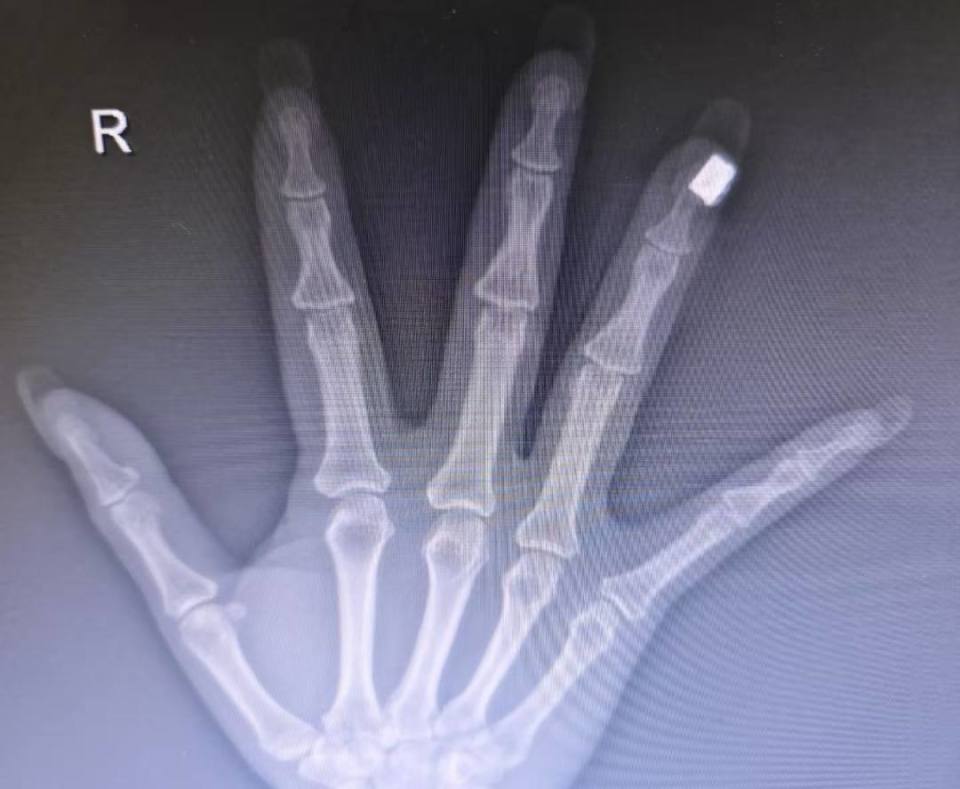

“有一次我在急诊接诊一位手外伤患者,给她拍手部X光时,意外发现美甲区域出现了高密度影,这说明美甲里面含有金属成分。”刘伟仔细观察后发现,患者的美甲上装饰有珠子或类似钻石的点缀,“外表看起来像是塑料或人造钻,但内核应该含有金属成分。”

图片

刘伟此前遇到的案例